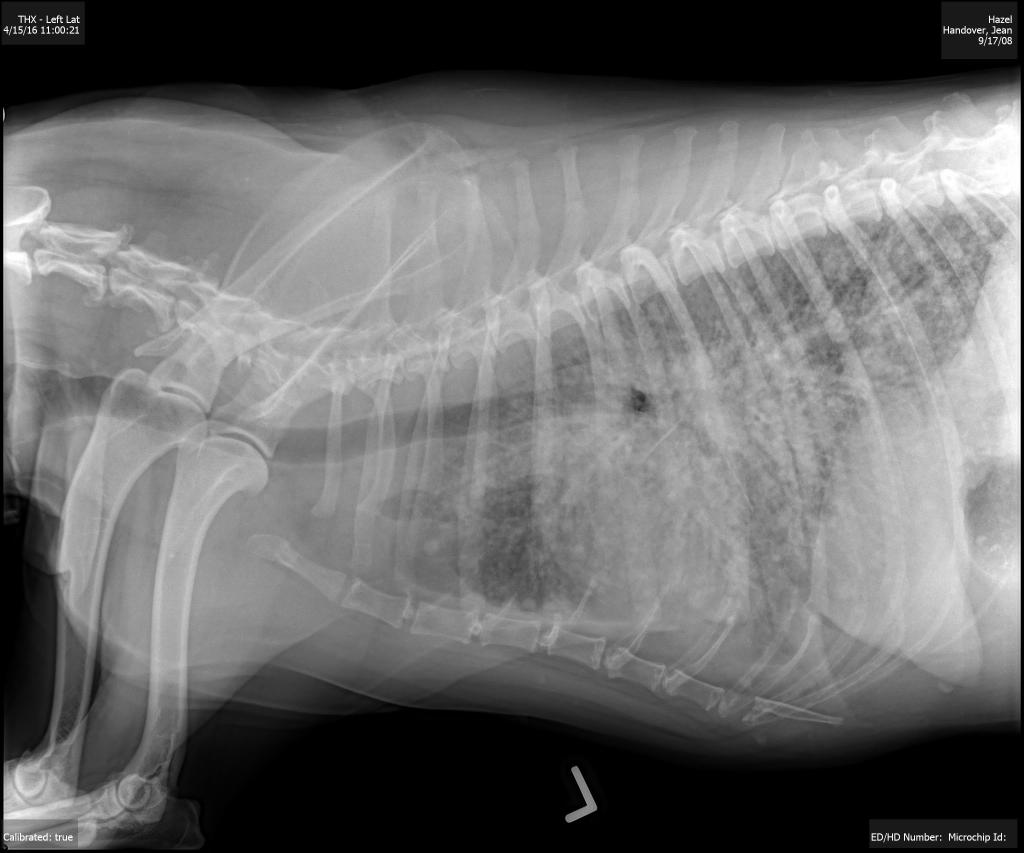

This can be more readily seen if I publish the xray image of yesterday and the image taken on the 15th April; see below.

One of the radiographs taken of Hazel.

One of the radiographs taken of Hazel 15th April, 2016.

Despite not truly understanding these images both Jean and I quickly thought the top one, taken yesterday, showed a decline in Hazel’s lungs compared to the lower one, taken on the 15th April.

Dr. Winters couldn’t be sure without a physical examination of the lung tissue but on the balance of probability she believed Hazel was at an advanced stage of cancer with the tumor somewhere in the body and that her lungs were showing that the cancer had metastasized!